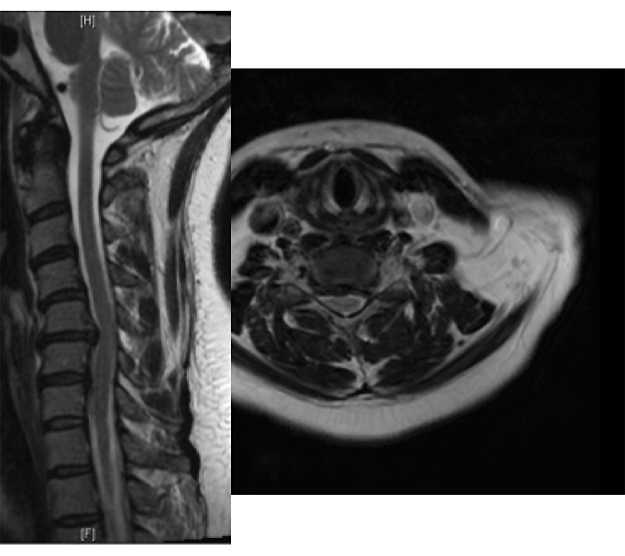

The intervertebral disc is a shock absorber that is located between the bony vertebral bodies in the neck, upper and lower back. It is composed of a firm outer layer and a gelatinous inner layer. When the outer layer is injured, the inner layer is extruded and can result in a pinched nerve. While common in professional football players, these injuries are not limited to contact sports as Major League Baseball players such as Nick Markakis and Prince Fielder have all been diagnosed with a herniated disc in their neck.

Most commonly, a herniated disc pinches a nerve after it has branched off of the spinal cord, and the injury results in shooting pain that starts in the neck and extends down one arm. In severe cases, this can be associated with arm numbness and weakness. While all athletes who experience these symptoms should see a medical professional, rest and anti-inflammatory medication will alleviate these symptoms in the vast majority of patients; however complete resolution of symptoms can take weeks to months. Strenuous athletic activity in the setting of ongoing symptoms is not recommended as this may worsen the symptoms.

Rarely, herniated discs in the neck can lead to compression on the spinal cord. This often leads to difficulty with balance, numbness and tingling in the hands, weakness is the arms and legs and rarely difficulty controlling one’s bowels and bladder. If any of these symptoms are present, athletes should seek immediate medical care, as prompt surgical intervention may be needed.